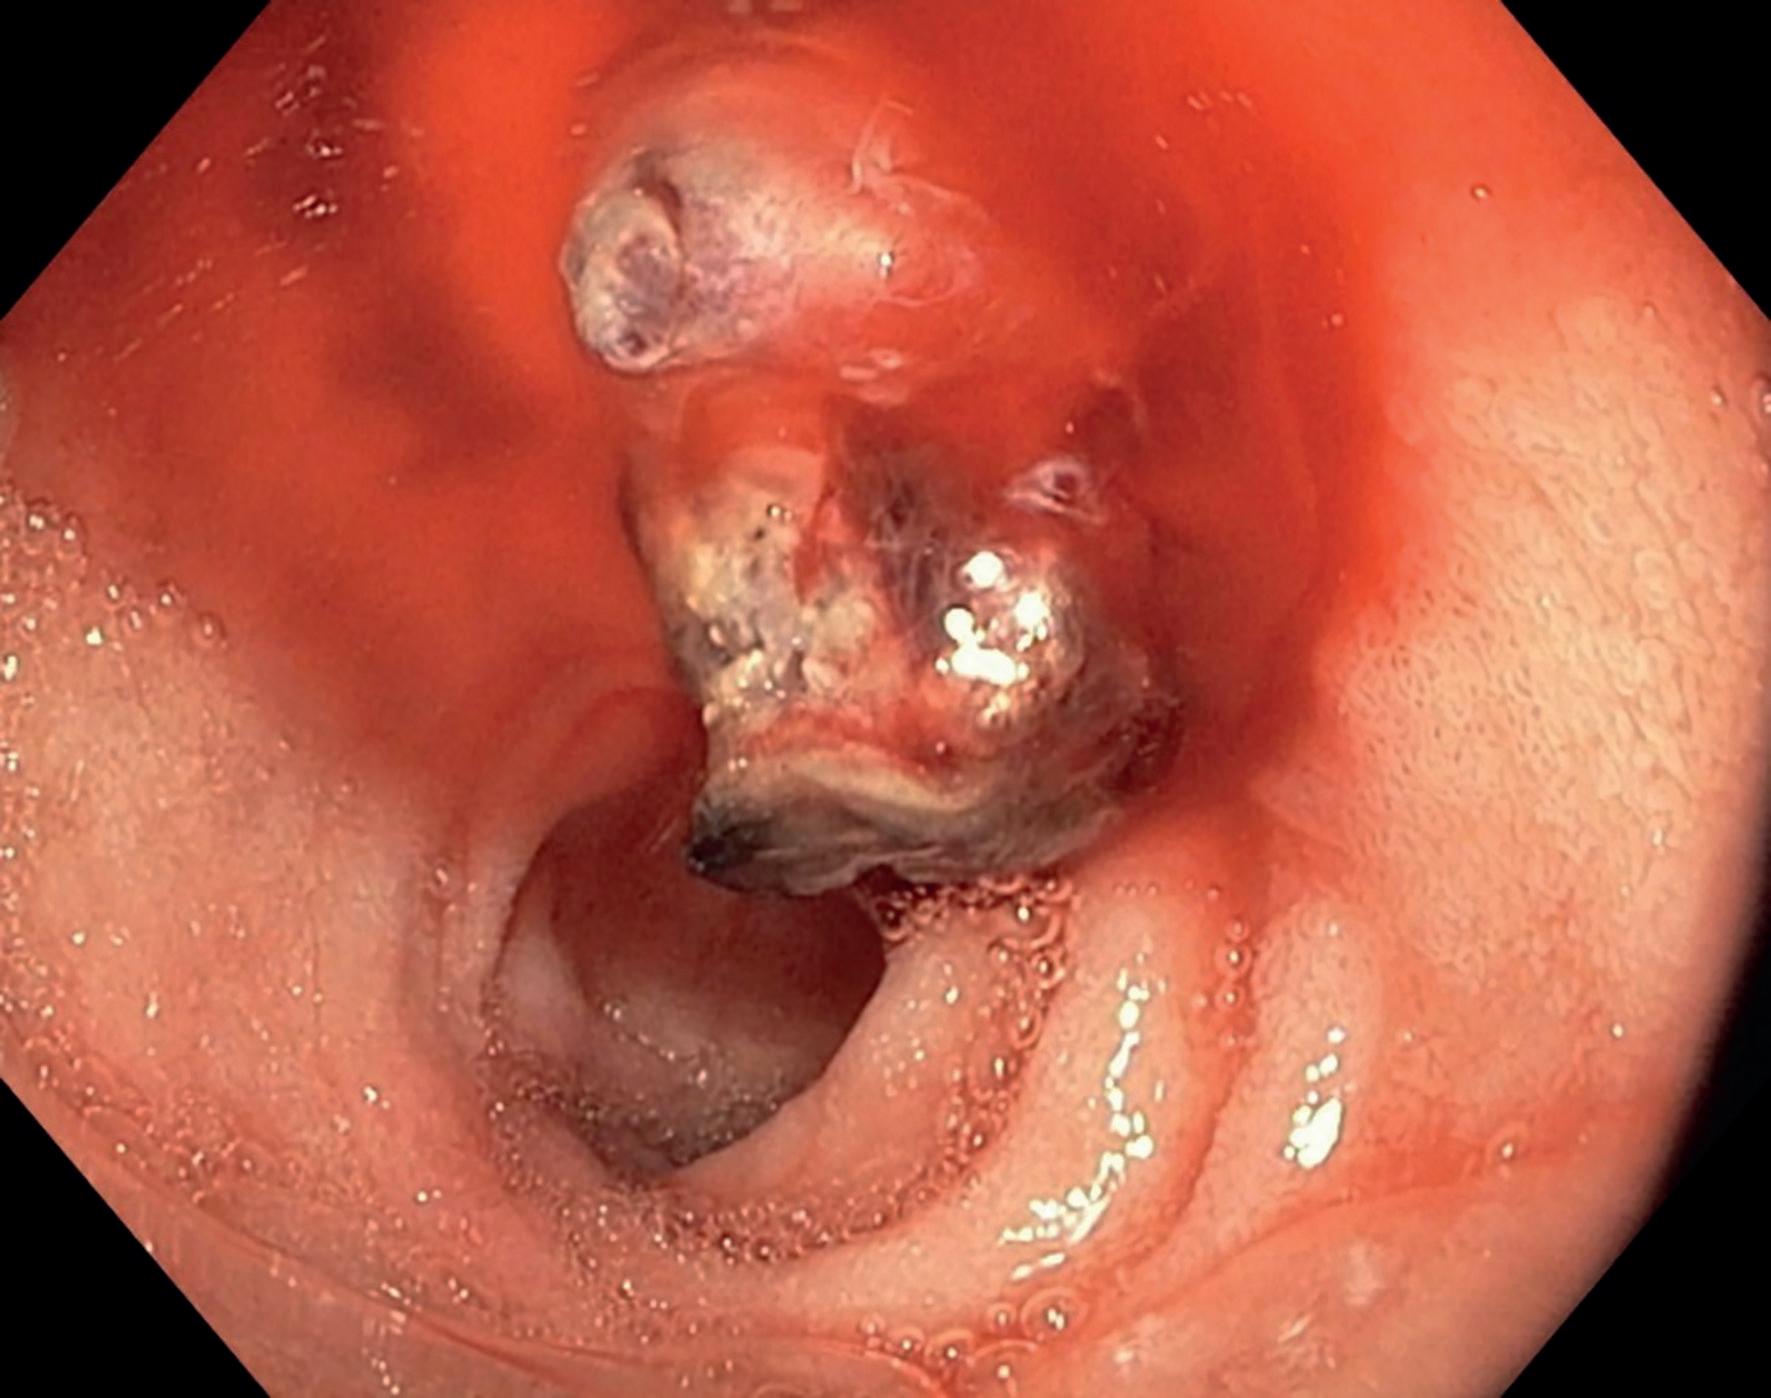

den må likevel behandles da lesjoner kan fortsette å vokse og skape skade lokalt. BCC-lesjoner er ofte gjennomsiktige med rosa, perlelignende nodul og med telangiektasier på overflaten (bilde 1 og 2). BCC klassifiseres som nodulære, mikronodulære, superfisielle, infiltrerende, morfea-type og basoskvamøse. De tre sistnevnte regnes som de mest aggressive, med høyest risiko for residiv og infiltrerende vekst.

Plateepitelkarsinomer kan variere mer i utseende, men starter ofte med en tørr, flassende flekk som etter hvert utvikler seg til et sår som ikke heles (bilde 3 og 4). De kan være flate eller store som et horn. I motsetning til BCC har 3-7 % av plateepitelkarsinomene metastasepotensiale (8). Aktinisk (solar) keratoser (AK) kan utvikle seg til plateepitelkarsinom. Det er vanskelig å vurdere risikoen for at en enkelt AK skal utvikle seg til plateepitelkarsinom, derfor anbefales det å fjerne AK.